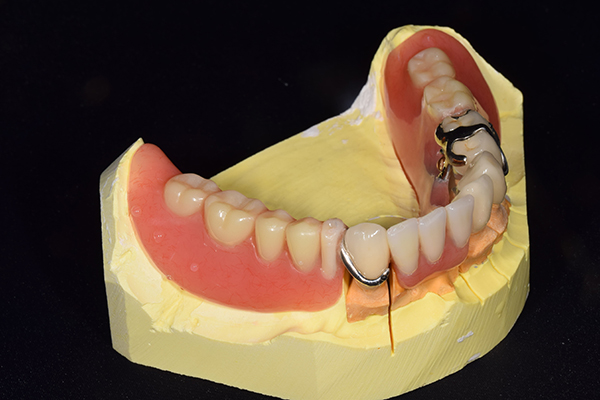

完成した入れ歯とかぶせ物です。 入れ歯への寛容度が高い患者様でしたので、 金属は使用せず、プラスチックのみで上は仕上げました。 下顎も歯は1本減ってしまいましたが、しっかり 入れ歯が維持できる様な構造にしました。

入れ歯は極力薄くするために金属を使用しました。しっかり噛める様にするため、ノンメタルクラスプデンチャーにはしませんでした。

上の入れ歯(表)

上の入れ歯(裏)

下の入れ歯

こちらが完成したかぶせ物と入れ歯です。かぶせ物にはアタッチメントをつけて金属のバネが見えない構造になっています。 入れ歯自体も金属を使用して、極力違和感がでないように、薄く作成しました。